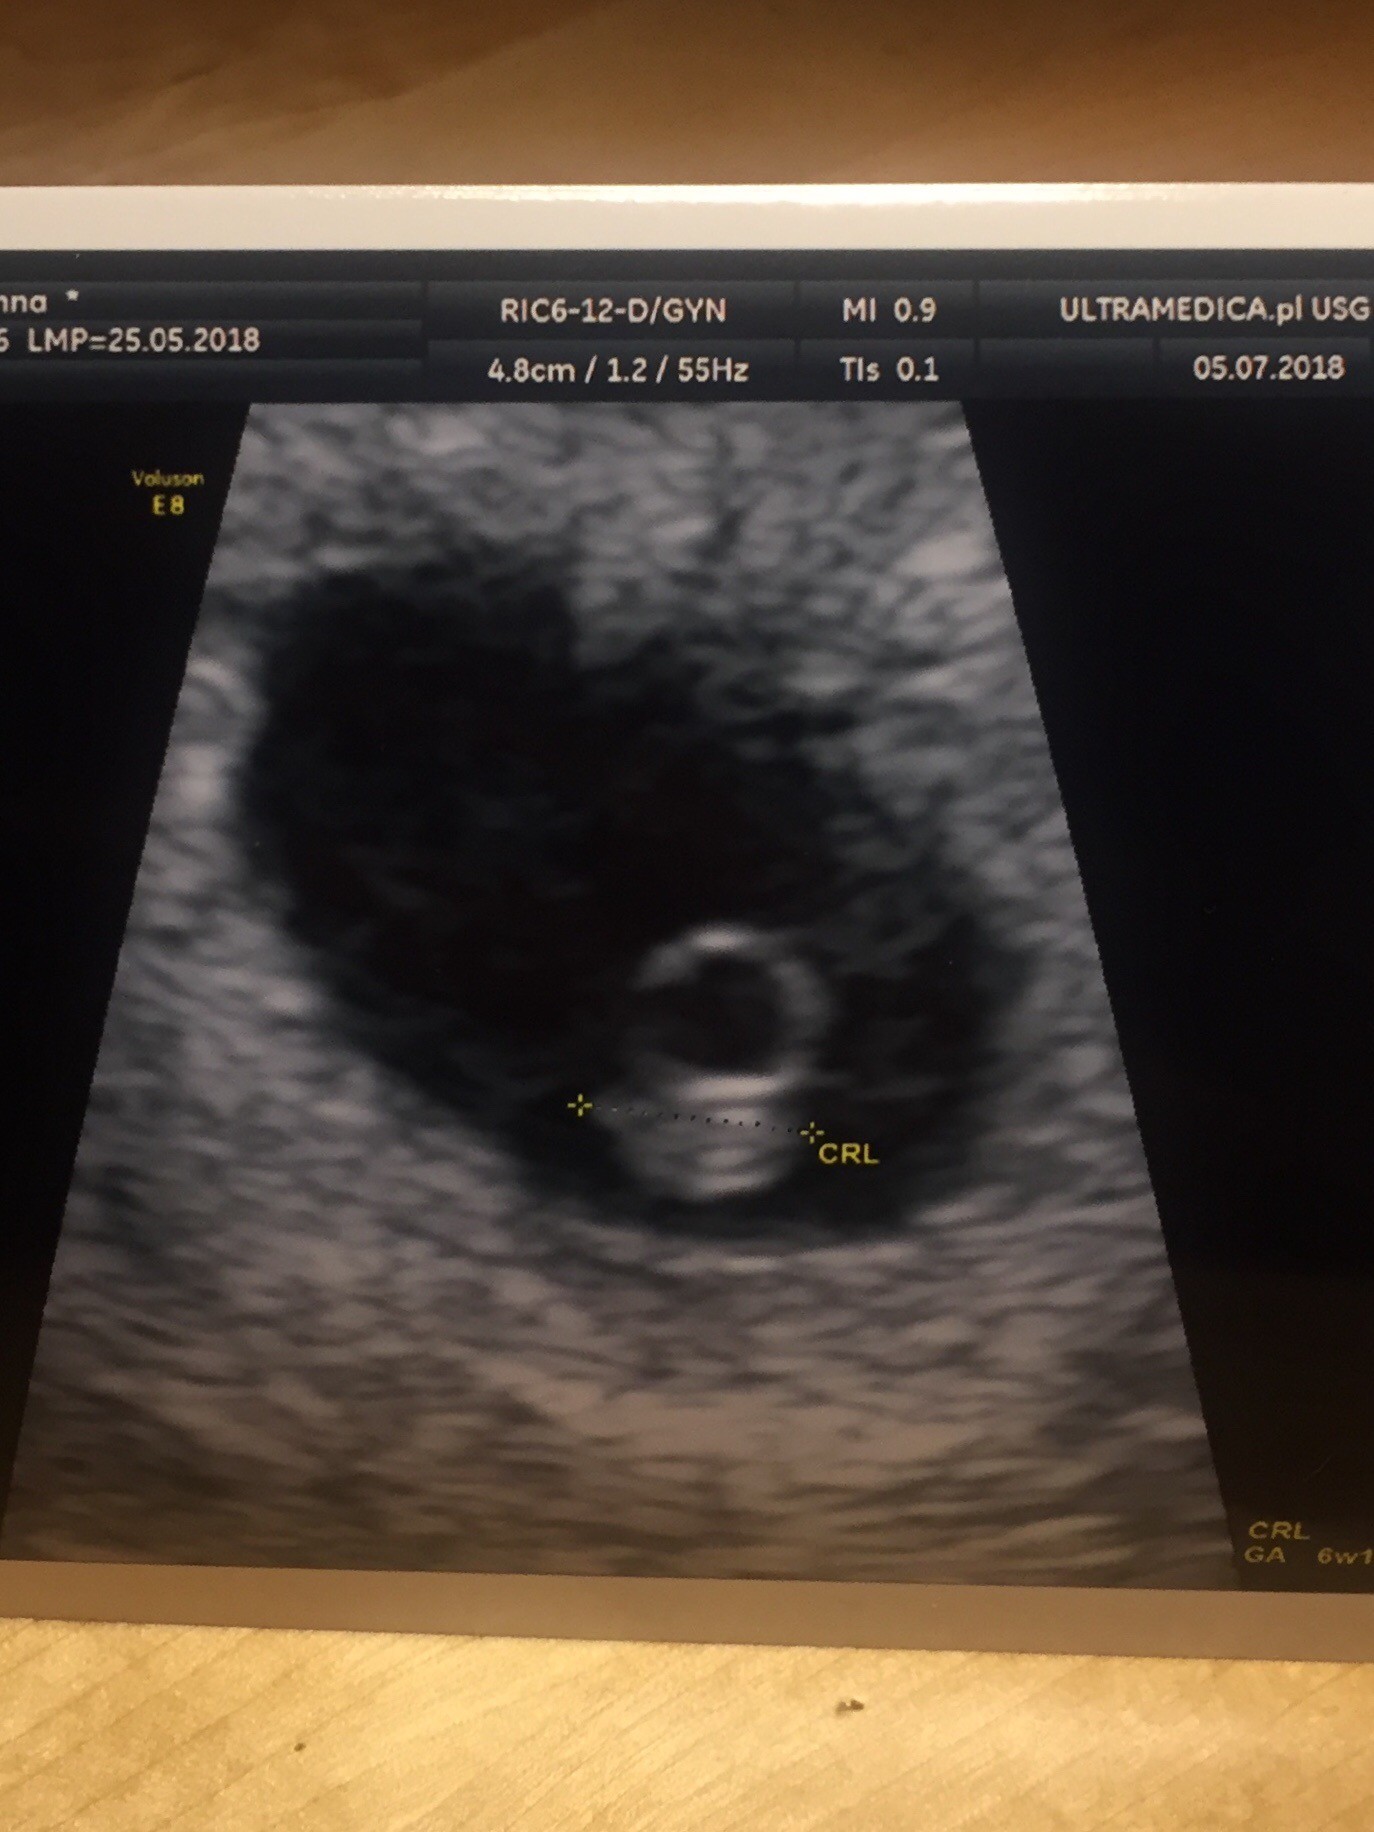

Termin porodu wg Naegelego : 1.03.2019

Statystyczny termin porodu wg CRL : 26.02.2019

Aktualny wiek ciążowy wg ostatniej miesiączki : 5+6

Wiek ciążowy na podstawie średnicy pęcherzyka : 6+4

Wszystko w jak najlepszym porządku, ciąża wyglada obiecująco.